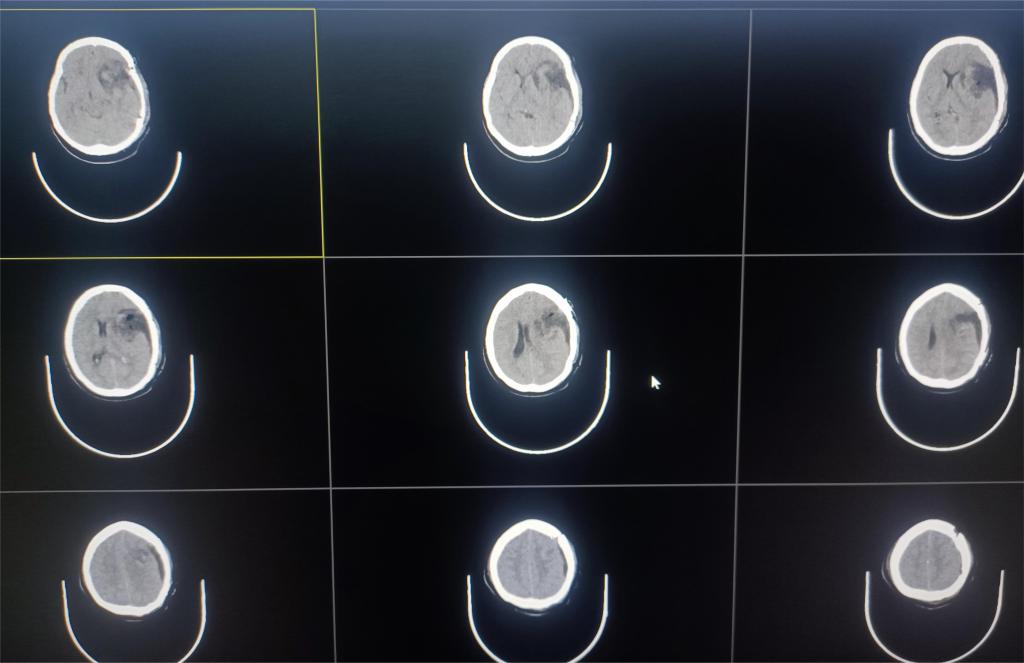

手术过程中,可见巨大肿瘤组织对正常脑组织压迫明显,局部与重要血管关系密切,在医护团队的密切配合及精细操作下,最终成功将肿瘤完整切除(图二)。

图二